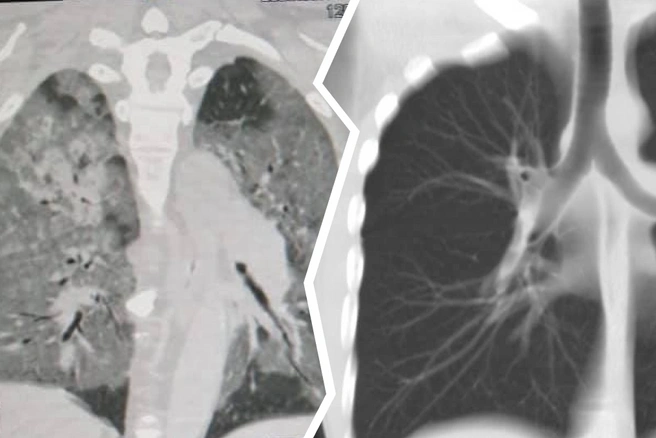

— Количество тяжелых пневмоний существенно выросло, у каждого такого больного мы берём биологический материал на исследование по COVID-19 и отправляем в специализированную лабораторию. Больных с клиникой новой коронавирусной инфекции на машинах скорой медицинской помощи отправляем согласно маршрутизации. Нагрузка на врачей и бригады скорой помощи колоссальная, — написал Харчиков. — Пожалуйста, соблюдайте масочный режим, носите перчатки, пользуйтесь кожным антисептиком, избегайте лишних контактов. — И на память — фотоснимки с компьютерного томографа, сделанные 14 мая в Переславской ЦРБ.

Врач прикрепил к посту фотографии легких больного с двухсторонней пневмонией и для сравнения легкие здорового человека.